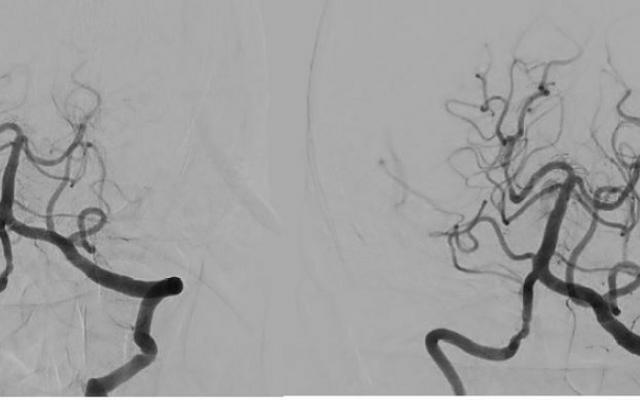

De A. basilaris verzorgt de bloedvoorziening van het achterste deel van de hersenen, inclusief de hersenstam. Een afsluiting van deze arterie leidt vaak tot ernstige neurologische uitvalsverschijnselen, zoals tetraparese of coma, en heeft een hoge mortaliteit. De BASICS-registratie (BASICS staat voor ‘Basilar artery international cooperation study’), een wereldwijde, observationele studie, liet zien dat de toegepaste therapie bij patiënten met een acute afsluiting van de A. basilaris sterk varieert tussen verschillende centra, terwijl er niet één behandeling is die de kans op een goede uitkomst duidelijk vergroot.1 Dit geldt in het bijzonder voor de intra-arteriële behandeling. Neurologen moeten zich dus goed realiseren dat het nut van intra-arteriële behandeling niet is aangetoond bij deze patiëntengroep, in tegenstelling tot bij patiënten met een intracraniële afsluiting in de voorste hersencirculatie.2

De BASICS-trial is een internationale studie, waarin patiënten met een symptomatische, acute afsluiting van de A. basilaris worden gerandomiseerd tussen de beste medicamenteuze behandeling of de beste medicamenteuze behandeling met aanvullende intra-arteriële behandeling. Het moet mogelijk zijn binnen 6 h na het ontstaan van de A.-basilarisafsluiting te beginnen met de intra-arteriële behandeling. Ook patiënten met een contra-indicatie voor intraveneuze trombolyse komen in aanmerking.